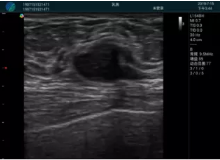

腺體內(nèi)部清晰顯示一低回聲塊影,形態(tài)不規(guī)則,邊界模糊,邊緣呈毛刺狀,內(nèi)部見(jiàn)砂礫樣鈣化

M20引導(dǎo)下穿刺活檢術(shù)

M20引導(dǎo)下平面內(nèi)穿刺取出的腫塊組織